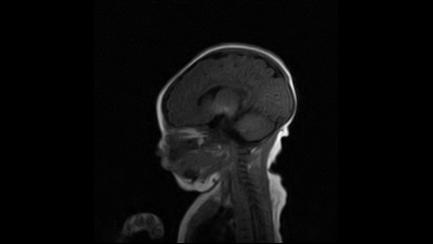

标题: PED3413:患儿女6天体检

缺血缺氧性脑病

6天为新生儿,髓鞘发育正常;左侧颞顶叶蛛网膜下腔增宽,请结合临床。

1。缺血缺氧性脑病2。左侧颞顶叶外部性脑积水,可观察

半卵圆中心上方层上可见对和乐大脑皮质t1高信号,考虑有hie可能,不知有何症状,建议加做dwi及复查

符合缺氧缺血性脑病影像表现。